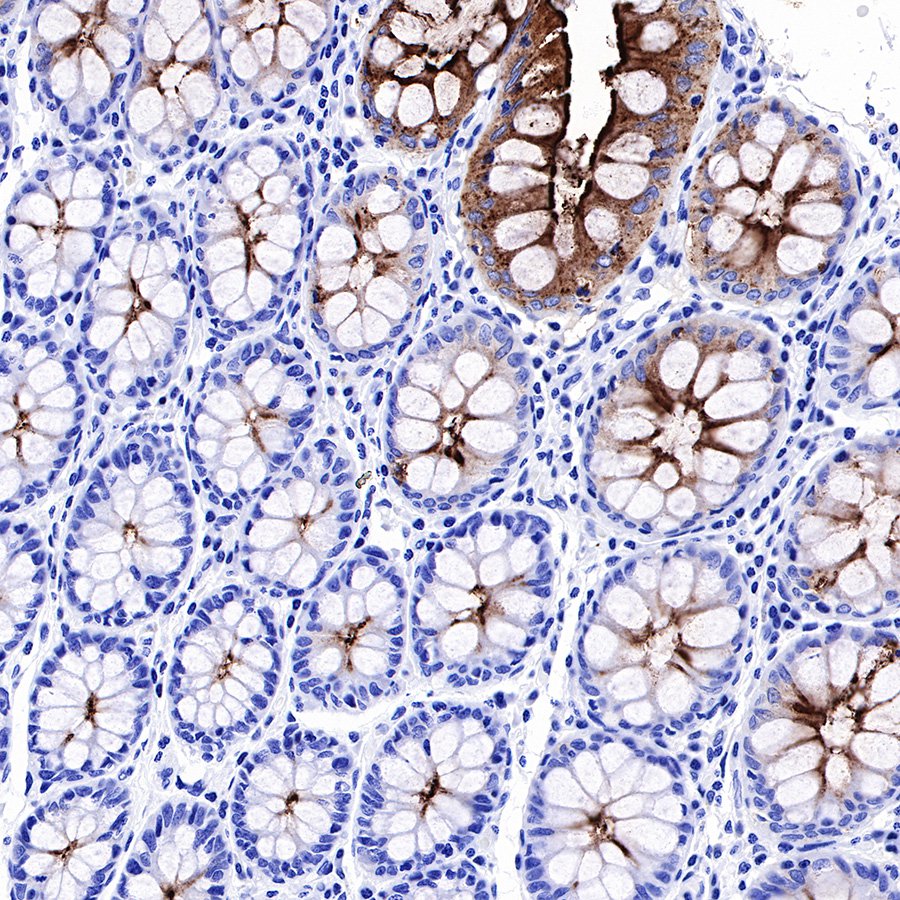

IHC shows positive staining in paraffin-embedded human colon. Anti-CEA(CD66e) antibody was used at 1/1000 dilution, followed by a Goat Anti-Rabbit IgG H&L (HRP) ready to use. Counterstained with hematoxylin. Heat mediated antigen retrieval with Tris/EDTA buffer pH9.0 was performed before commencing with IHC staining protocol.